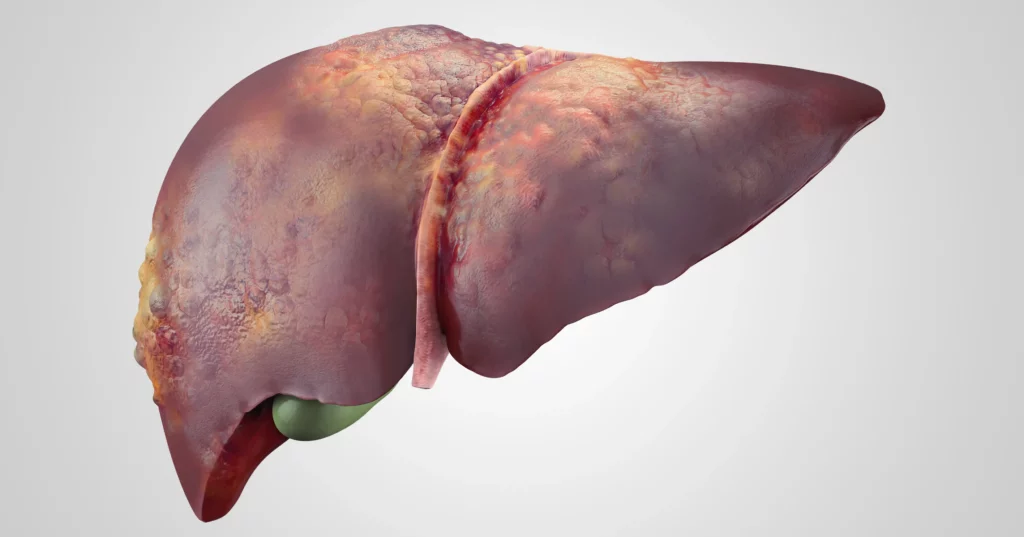

Ciroza je otvrdnuće jetre zbog ožiljnog tkiva. Ožiljno tkivo zamenjuje ćelije jetre u procesu poznatom kao fibroza. Na kraju, fibroza može dovesti do otkazivanja jetre jer je funkcionalnost ćelija jetre uništena. Ovo stanje može biti uzrokovano brojnim faktorima. Toksini, prekomerna upotreba alkohola i virusi poput hepatitisa su česti uzroci ciroze. Dijabetes, problemi sa imunitetom i genetske bolesti takođe mogu izazvati cirozu jetre.

Komplikacije nastaju kada je regeneracija jetre ili nepotpuna ili sprečena progresivnim razvojem ožiljnog tkiva u jetri. Ovo se dešava kada štetni agens kao što je virus, lek, alkohol itd. nastavi da napada jetru i spreči potpunu regeneraciju. Kada se ožiljno tkivo razvije, veoma je teško preokrenuti proces regeneracije. Teški ožiljci na jetri su karakteristični za stanje poznato kao ciroza. Razvoj ciroze ukazuje na kasnu fazu bolesti jetre i obično je praćen pojavom komplikacija.